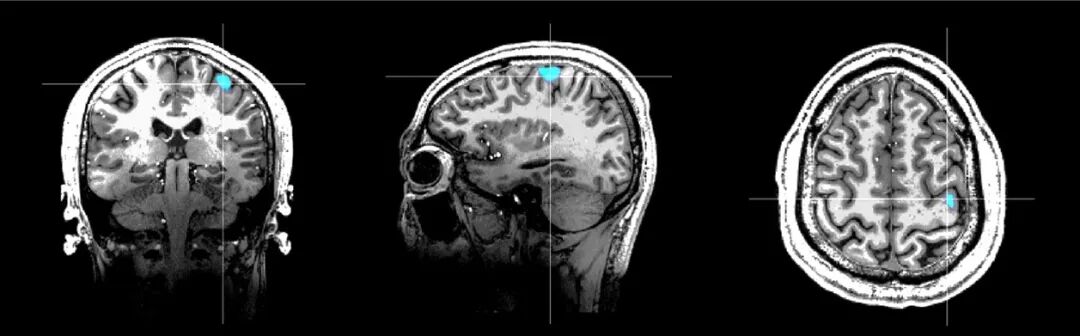

Marvel MEG®脑磁图仪健康人右手运动功能区与7.0T核磁影像融合结果